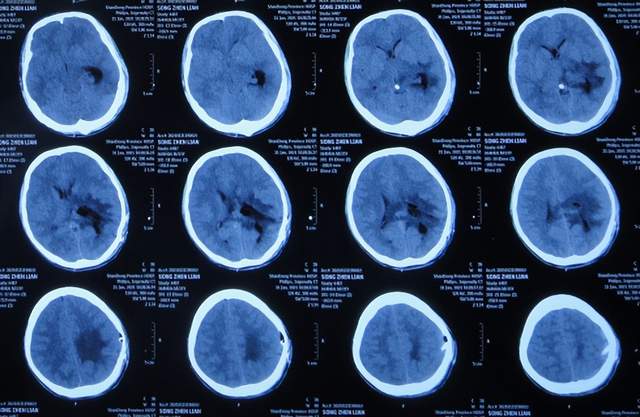

继续抗感染治疗1周的时间,仍精神差,食欲差,间断发热,期间3次查头颅影像(2021年1月29日头颅核磁增强(图-10)、2021年1月31日头颅CT(图-11)、2021年2月3日头颅核磁增强(图-12)均示颞角逐渐有扩张,有感染。

图-10:2021年1月29日头颅核磁增强

图-11:2021年1月31日头颅CT

图-12:2021年2月3日头颅核磁增强

2021年2月5日(脑膜瘤切除术后颅内感染3周)住入李小勇脑脊液科,入院时:精神差,食欲差,体温高(图-13);查头颅CT示脑瘤术后状态(图-14);(外院)2021年2月3日头颅核磁示有脑脓肿(图-12)。

图-13:2021年2月5日入院时

图-14:2021年2月5日头颅CT

入院后3天即2021年2月8日,左颞角脑室腹壁外引流术(图-15)。

图-15:2021年2月8日头颅CT

左颞角脑室腹壁外引流术后8天即2021年2月16日,查头颅CT示颞角缩小(图-16)。

图-16:2021年2月16日头颅CT

左颞角脑室腹壁外引流术后21天即2021年3月1日,查头颅CT示颞角仍有扩张(图-17)。

图-17:2021年3月1日头颅CT

左颞角脑室腹壁外引流术后23天即2021年3月3日,头颅CT增强和核磁增强示有脑脓肿(图-18、图-19)。

图-18:2021年3月3日头颅CT增强

图-19:2021年3月3日头颅核磁增强

2021年3月8日(左颞角脑室腹壁外引流术后28天),进行了脑脓肿切除术(图-20)。

图-20:2021年3月8日头颅CT

2021年3月9日(左颞角脑室腹壁外引流术后29天,脑脓肿切除术后次日),查头颅CT示脑脓肿切除术后(图-21)。

图-21:2021年3月9日头颅CT